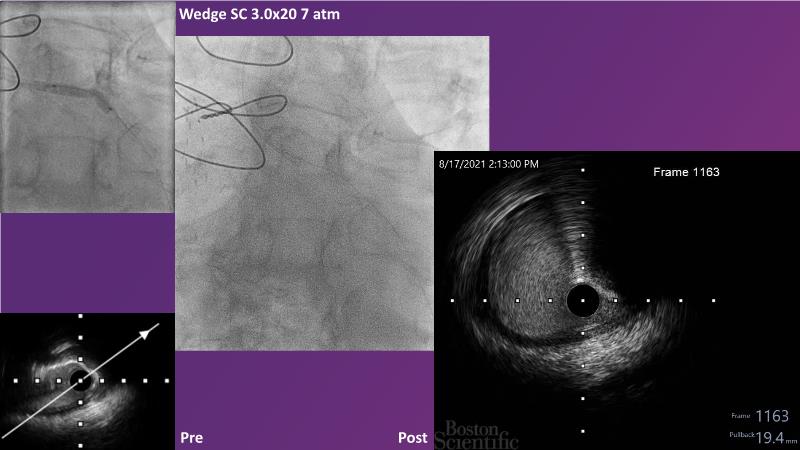

Don't miss this session for expert guidance on preparing and managing complex lesions. Gain insights into choosing the right tools, including microcatheters and balloons, for optimal treatment outcomes. Explore the innovative features of flagship devices for complex PCI, and Pronavi microcatheter and Alveo HP CTO balloon to treat complex CTO lesions. Learn about the safety and efficacy of the Wedge NC scoring balloon, the importance of using POT dedicated balloons in POT and DOT techniques, and get updated tips and tricks from ongoing clinical practices.

- To gain insights on Pronavi microcatheter and Alveo HP CTO balloon to treat complex CTO lesions, understand the safety and efficacy of lesion preparation with Wedge NC scoring balloon and the significance of using POT dedicated balloon in POT and DOT technique